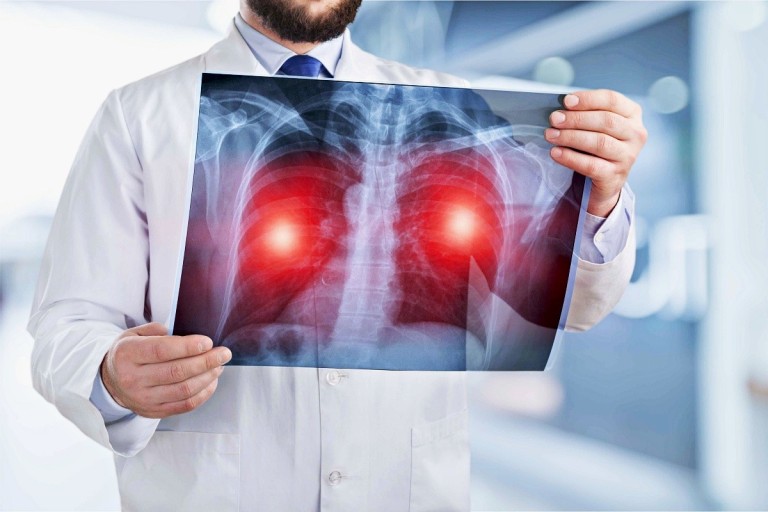

- 정기적인 건강 검진: 위와 같은 증상이 하나라도 나타나면 즉시 병원을 방문하여 흉부 X-ray, CT 촬영 등 검사를 받는 것이 중요합니다.